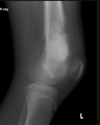

Cisto ósseo simples com fratura

Lesão litica unicameral.

Localização: úmero proximal e femur (< 20 anos) ou calcâneo, talus, ileo (> 20 anos).

Se fratura: Sinal do fragmento caído.